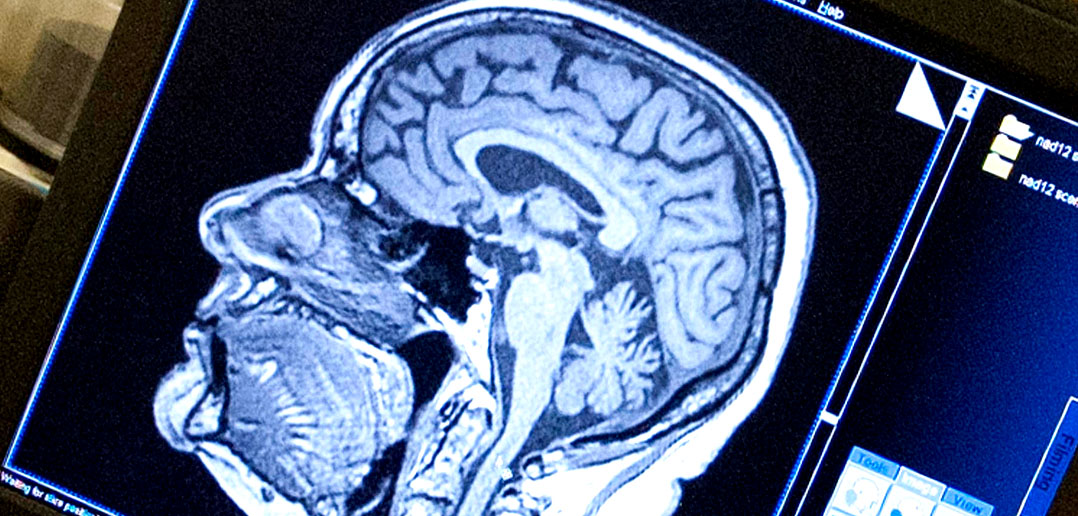

The facial expression related connectivity and that of one’s self and the surroundings are very. Autism is thought to result from miswired connections in the developing brain, and many experts believe that therapies must begin during a critical window. Rdi focuses on developing skills such as theory of mind, independent thinking, consideration of others, and more.